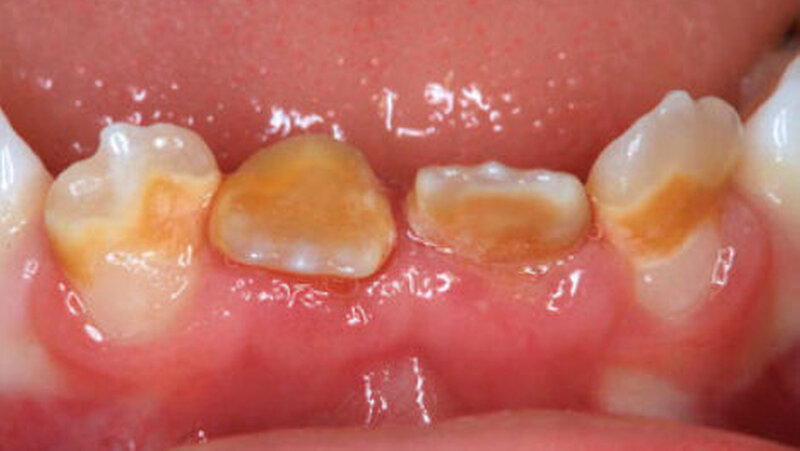

Dilazeration (Abb. 1 bis 7) kann zur Durchbruchsstörung des betroffen Zahns führen. Fast immer sind auch Farb- und Formanomalien des Schmelzes zu beobachten. Die Erhaltungsmöglichkeit solcher Zähne hängt primär von der Schwere und Lokalisation der Missbildung, aber auch vom Grad der Farb- und Strukturanomalie ab. Malformationen im mittleren oder apikalen Wurzeldrittel sind ohne Einfluss auf den dentogingivalen Verschluss und haben in der Regel wenig Einfluss auf den Zahnerhalt - die Pulpa bleibt hier in den meisten Fällen vital.

Bei ausgeprägten Missbildungen wie im beschriebenen Fall im Bereich des Zahnhalses ist der konservierende und endodontologische Zahnerhalt - obwohl angestrebt - oft nicht mehr möglich. Dies muss jedoch im Einzelfall diskutiert und entschieden werden.